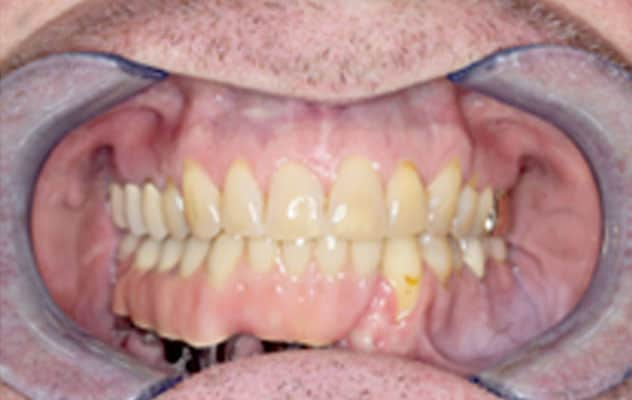

Final appearance

Image shows the final appearance with the prosthetic dental bridge in place.

The final dental prosthesis was inserted one month later. Nine years later, the patient is doing well and has had no tumor recurrence.